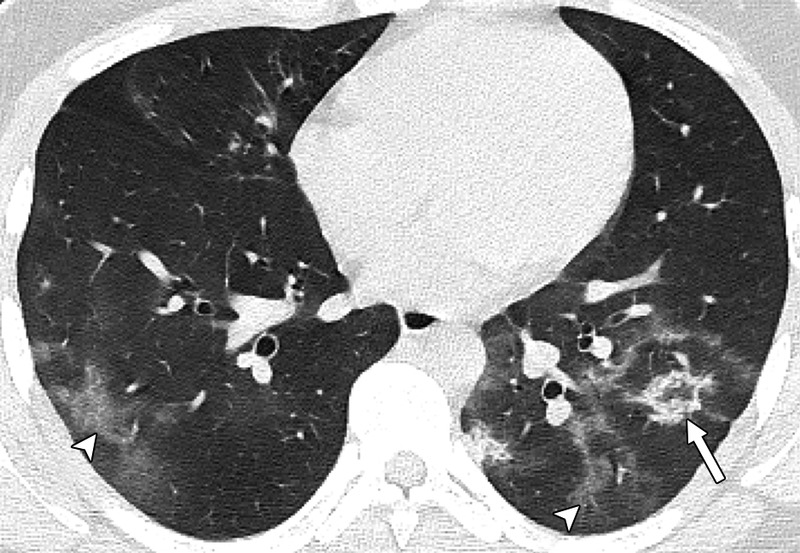

«Μία εικόνα χίλιες λέξεις. Αξονικές τομογραφίες νέων κάτω από 18 έτη με Covid-19 (18 ετών, 15 ετών, 14 ετών και 8 ετών). Κανένας ασθενής δεν είχε υποκείμενα νοσήματα ή ανοσοκαταστολή. Οι ασθενείς δεν χρειάστηκαν συμπληρωματικό οξυγόνο, διασωλήνωση ή ΜΕΘ. Πρόκειται για απλά-κοινά περιστατικά Covid-19. Ωστόσο έχουν πολύ «εντυπωσιακές» βλάβες και είναι άγνωστο τι θα προκαλέσουν αυτές οι βλάβες σε βάθος χρόνου. Για την πλειονότητα του κόσμου το ερώτημα είναι απλό: Θέλουν να υποβάλουν τους πνεύμονές τους σε αυτές τις βλάβες για να δουν αν αντέχουν; Και αν αντέξουν την πρόκληση (όπως προβλέπεται ότι θα αντέξουν οι περισσότεροι νέοι) θέλουν να δουν πόσα χρόνια ή αντοχές έχασαν στην πορεία; Με το εμβόλιο προστατεύουμε τους πνεύμονές μας από βαρύτατη καταπόνηση».